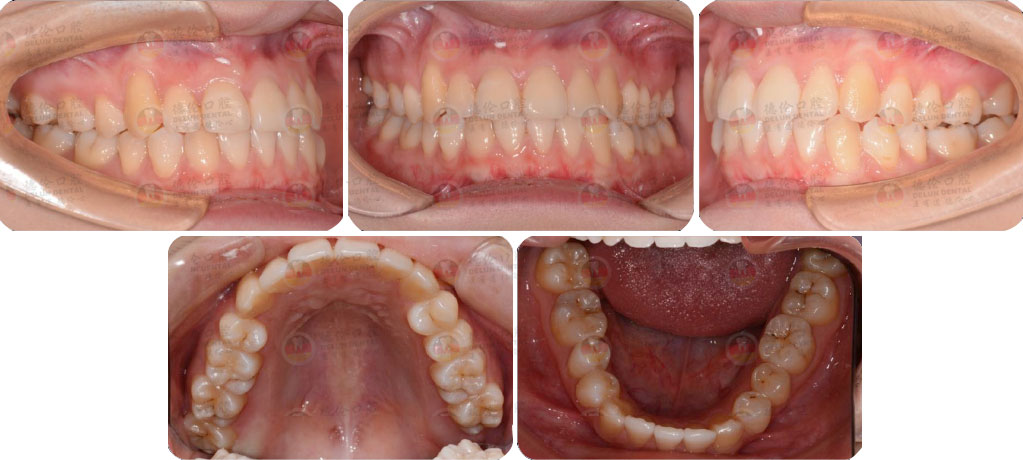

矯治前后對(duì)比

蛻變周期:上頜16個(gè)月,矯治效率提升30%,下頜12個(gè)月,矯治效率提升20%

矯

治

后

口

內(nèi)

照